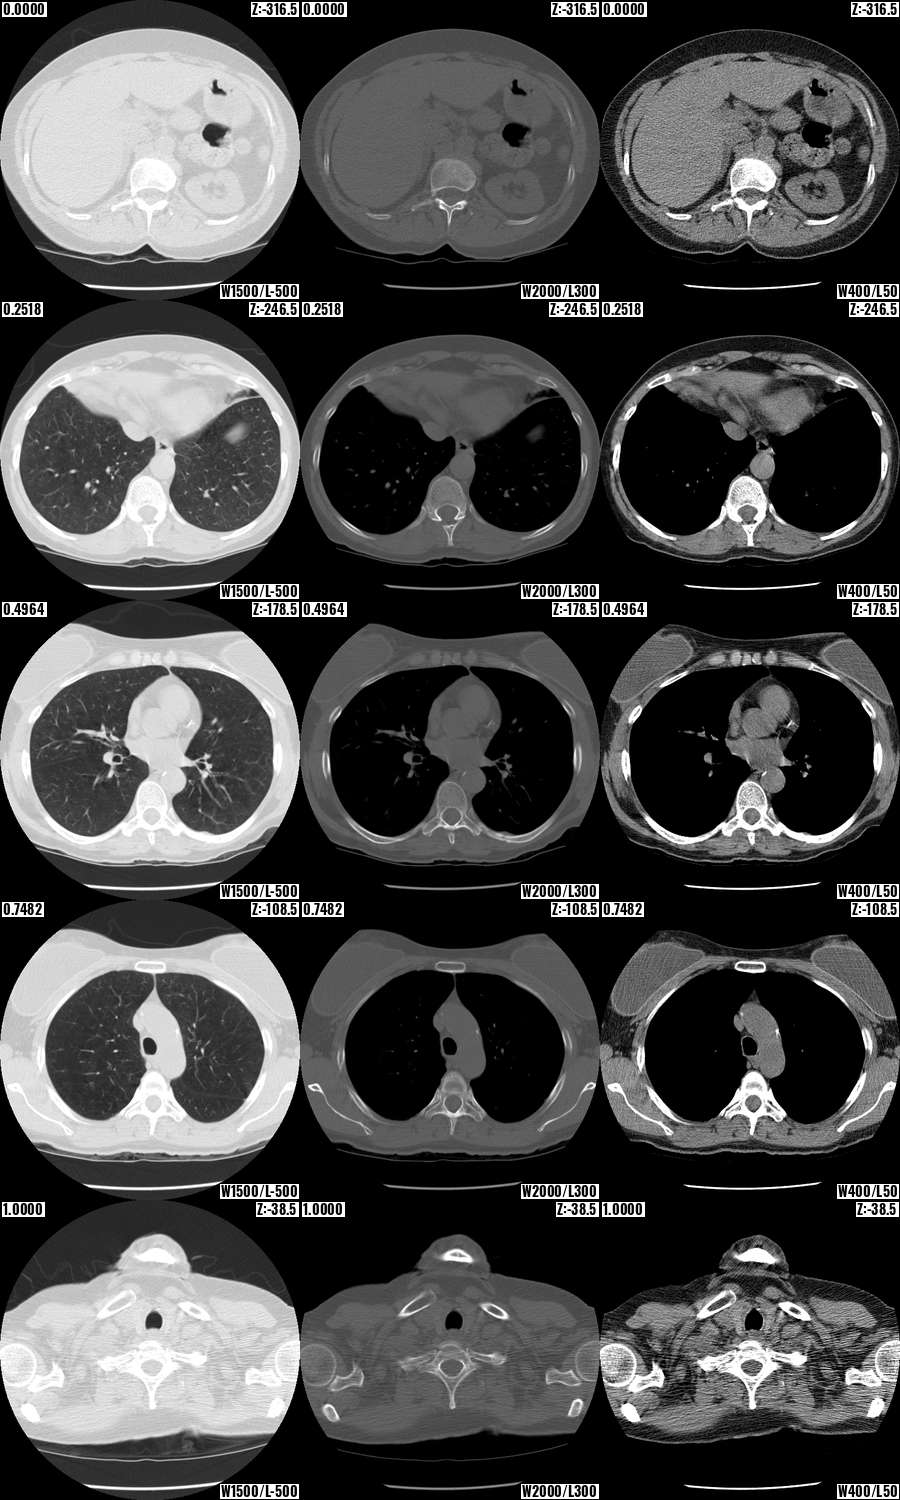

“Find the bottom of the lungs in an IDC NLST series”:

Base of lungs

Contrast Mosaic:

Contrast mosaic